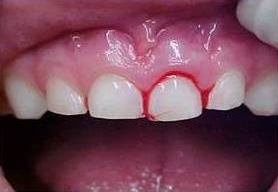

Trauma de concussão Fratura de parte da coroa dentária Frantura da raíz no Raio-x

É importante ressaltar que mesmo que pareça que o dano causado tenha sido mínimo, a visita ao seu dentista é fundamental. Ele irá avaliar através de exames complementares como raio-x, se não houve nenhum comprometimento dos tecidos adjacentes, bem como da raiz dentária.